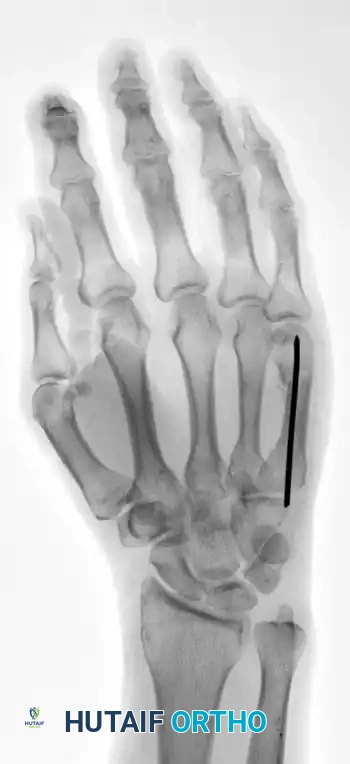

FIGURE 67-37A: Preoperative AP radiograph of a fourth metacarpal shaft fracture.

FIGURE 67-37B: Preoperative lateral radiograph of the fourth metacarpal fracture.

FIGURE 67-37C: Postoperative AP radiograph showing intramedullary fixation with a Kirschner wire.

FIGURE 67-37D: Postoperative lateral radiograph confirming anatomic restoration.

This technique is equally effective for mid-shaft fractures, as demonstrated in the fourth metacarpal example below: